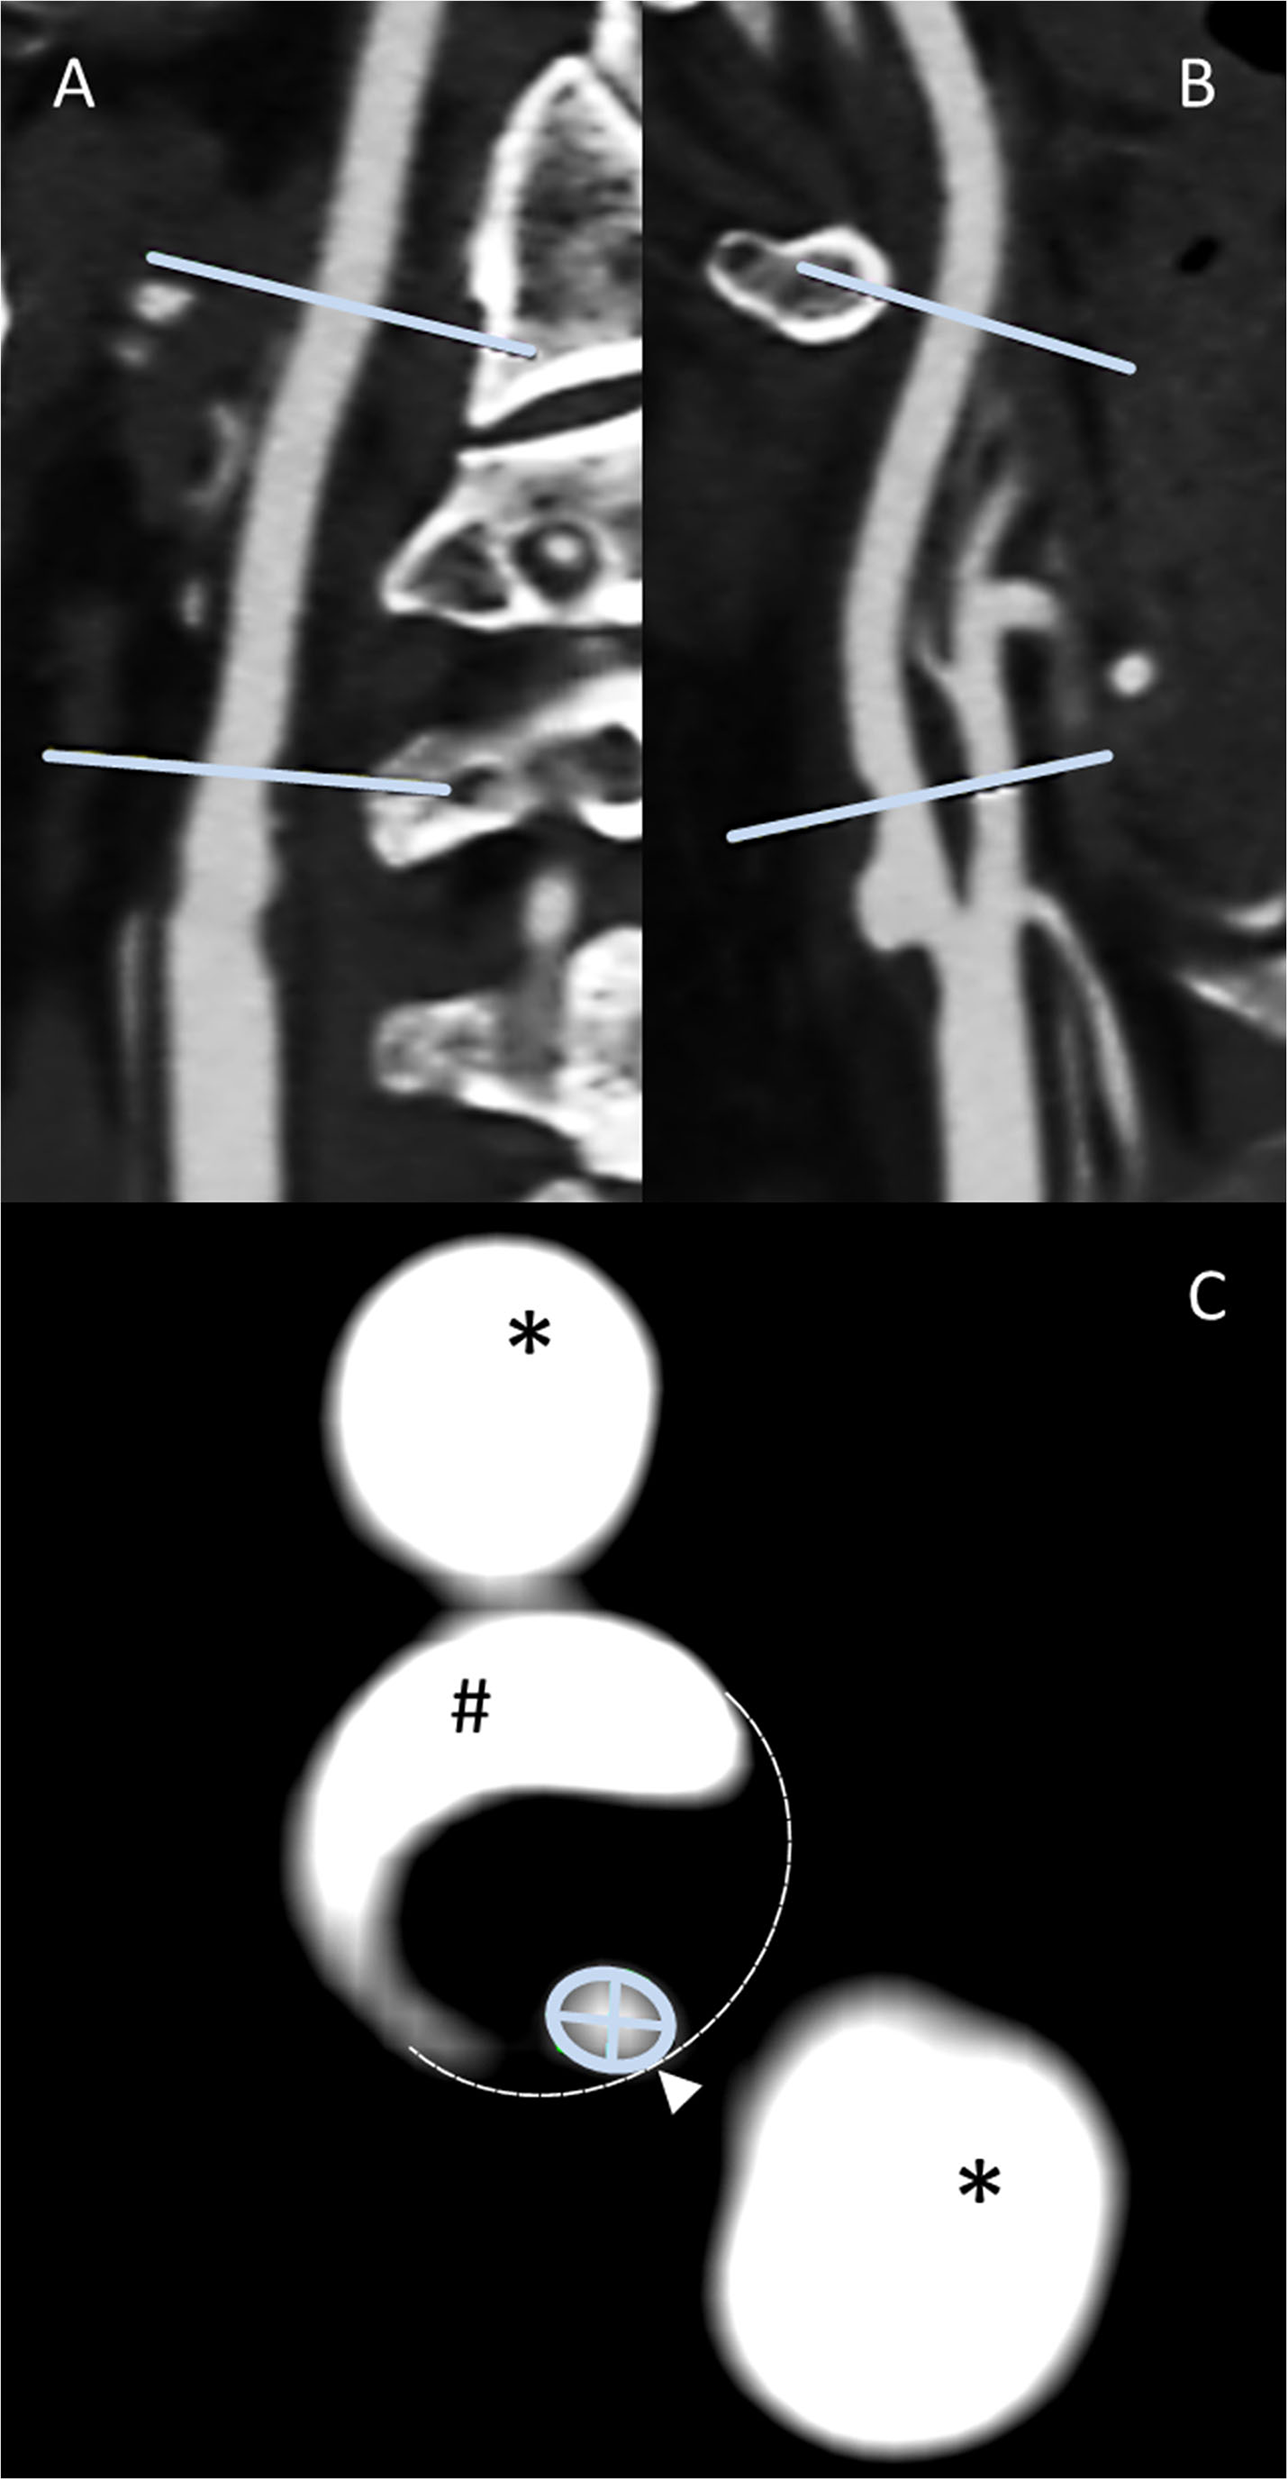

All manual image analyses were prospectively treated and analyzed by a physician with expertise in cerebrovascular imaging blinded to clinical and also any other imaging findings and outcomes. All quantitative measurements were supervised by an expert neuroradiologist (HHK). Obtained CTA raw data were initially screened for overall quality, carotid artery occlusion, and the presence of bifurcation calcifications. Initially, maximum intensity projection (MIP) allowed the exploration of vascular anatomy by increasing the artery-to-tissue contrast to define the presence and location of the ICA stenosis. Subsequently, the dataset was reformatted using MPR to generate consecutive and freely adjusted planes in respect of the ICA orientation allowing for precise measurement of the extent of the stenosis by minimal diameter measurements. Whereas, two MPR planes were set along the principal artery axis, the third was adjusted orthogonally to both planes and adapted in the presence of irregular stenosis. The standard Hounsfield scale center and window (c/w) were set to 250/600. In the presence of calcifications, c/w was adjusted individually to allow optimal differentiation between the calcified plaques and the endoluminal contrast media. Carotid stenosis grade was then measured using the NASCET method (13). This grading provided a ratio of the maximum stenotic narrowing (A) and the diameter of the far distal ICA beyond the stenosis and poststenotic dilation (C), calculated by [1-A/C × 100] (Figure 1).

Figure 1

Methodology panel, MPR-based ICA stenosis diameter measurements: sagittal (A) and coronal (B) multiplanar reconstructions allow the identification of both the non-stenotic distal diameter [NASCET (C)] and the stenosis region. After the adjustment of either the coronal or sagittal plane for the optimal perception of the stenotic vessel configuration along the stenotic segment principal orientation, the subsequent perpendicular axial reconstruction of excellent spatial CTA resolution allows the outstanding distinction of vascular pathology (C), that is, calcified plaque (#), non-contrasted soft plaque (area enclosed by dashed line), and residual ICA lumen (encircled by green line). This plane is used for locating the smallest diameter [NASCET (A)]. Finally, the minimum stenotic diameter can be measured defined as the smaller of the two measurable diameters. External carotid artery branches (*) appear as homogenously contrasted additional lumina.